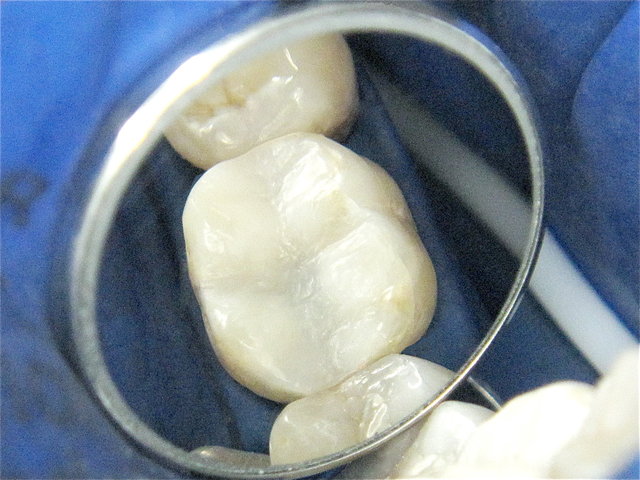

Alte undichte Amalgam-Füllungen mit Karies und Rissen ...

Composit-Füllungen by CLINICDENT ✓